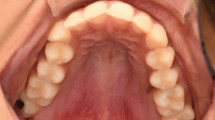

Necrotizing sialometaplasia is a self-limiting, variably ulcerated benign process affecting minor salivary glands. Accurate histological diagnosis is paramount, as it has been mistaken for malignancy, which has resulted in excessively aggressive and unnecessary radical surgery. A unique case of bilateral necrotizing sialometaplasia, presenting with anaesthesia of the greater palatine nerves, is described. An attempt at active therapy with intralesional steroids had no effect on the course of the condition.